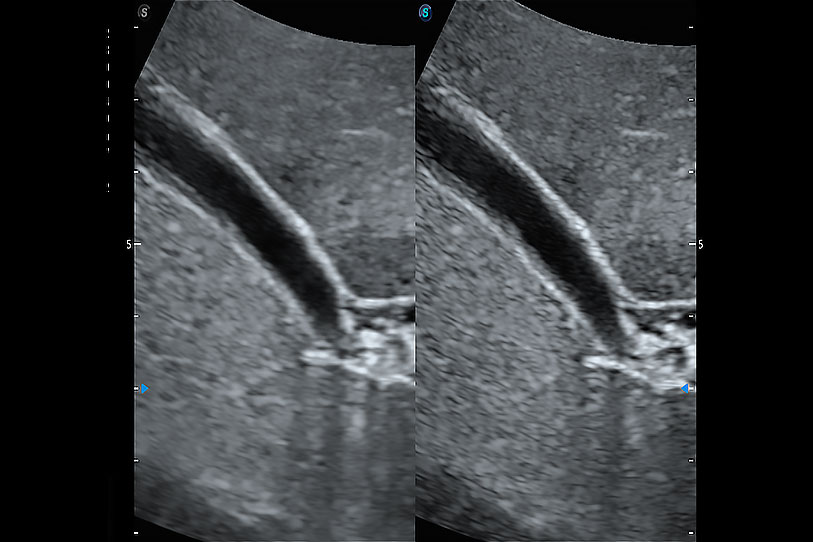

增強(qiáng)穿刺針在動(dòng)物解剖結(jié)構(gòu)中的位置,提高穿刺介入的安全性和準(zhǔn)確性。

為精細(xì)結(jié)構(gòu)及組織邊緣提供高清晰度的圖像和更大的成像視野。幫助減輕醫(yī)生的用眼疲勞,快速精準(zhǔn)獲得測(cè)量的數(shù)據(jù)。